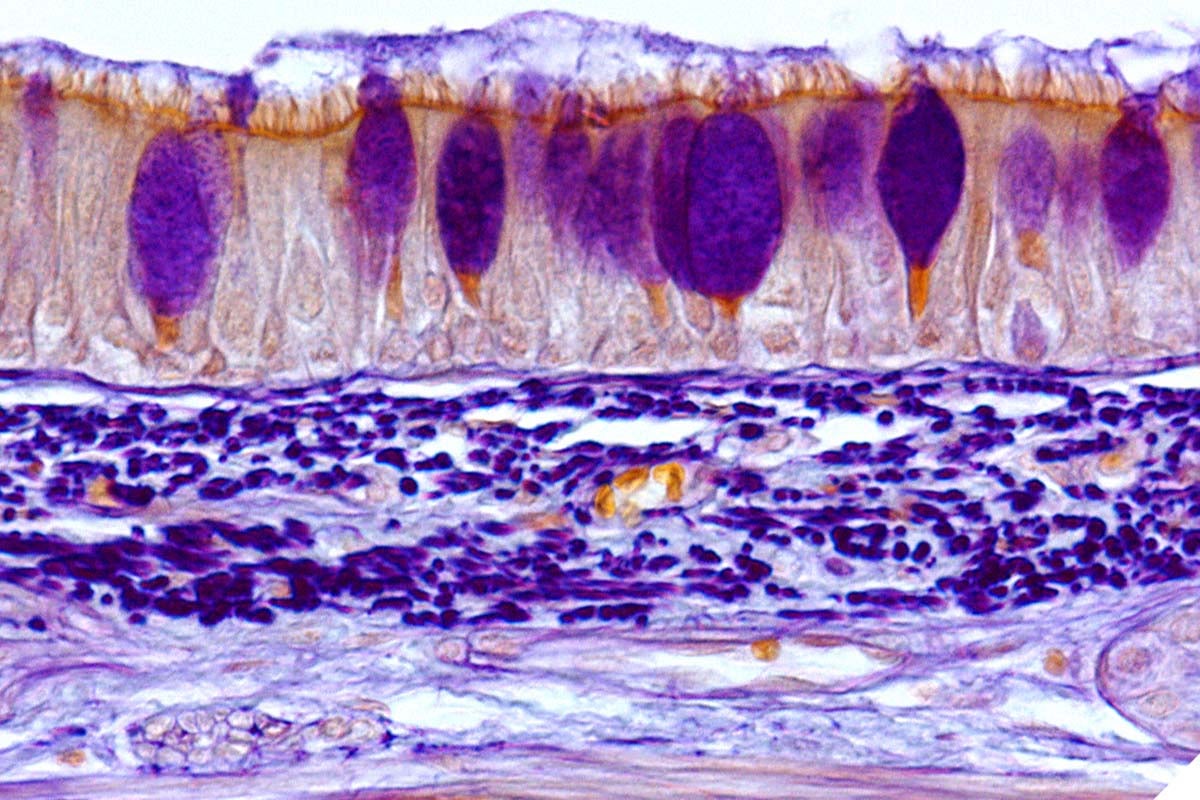

―炎症性腸疾患における粘膜再生治療の開発や腫瘍発生機構の解明に期待―2017-12-8 国立大学法人東京医科歯科大学,国立研究開発法人日本医療研究開発機構 大腸分泌系上皮細胞(ATOH1陽性細胞)は大腸幹細胞から分化し生体恒常性を維持してい...